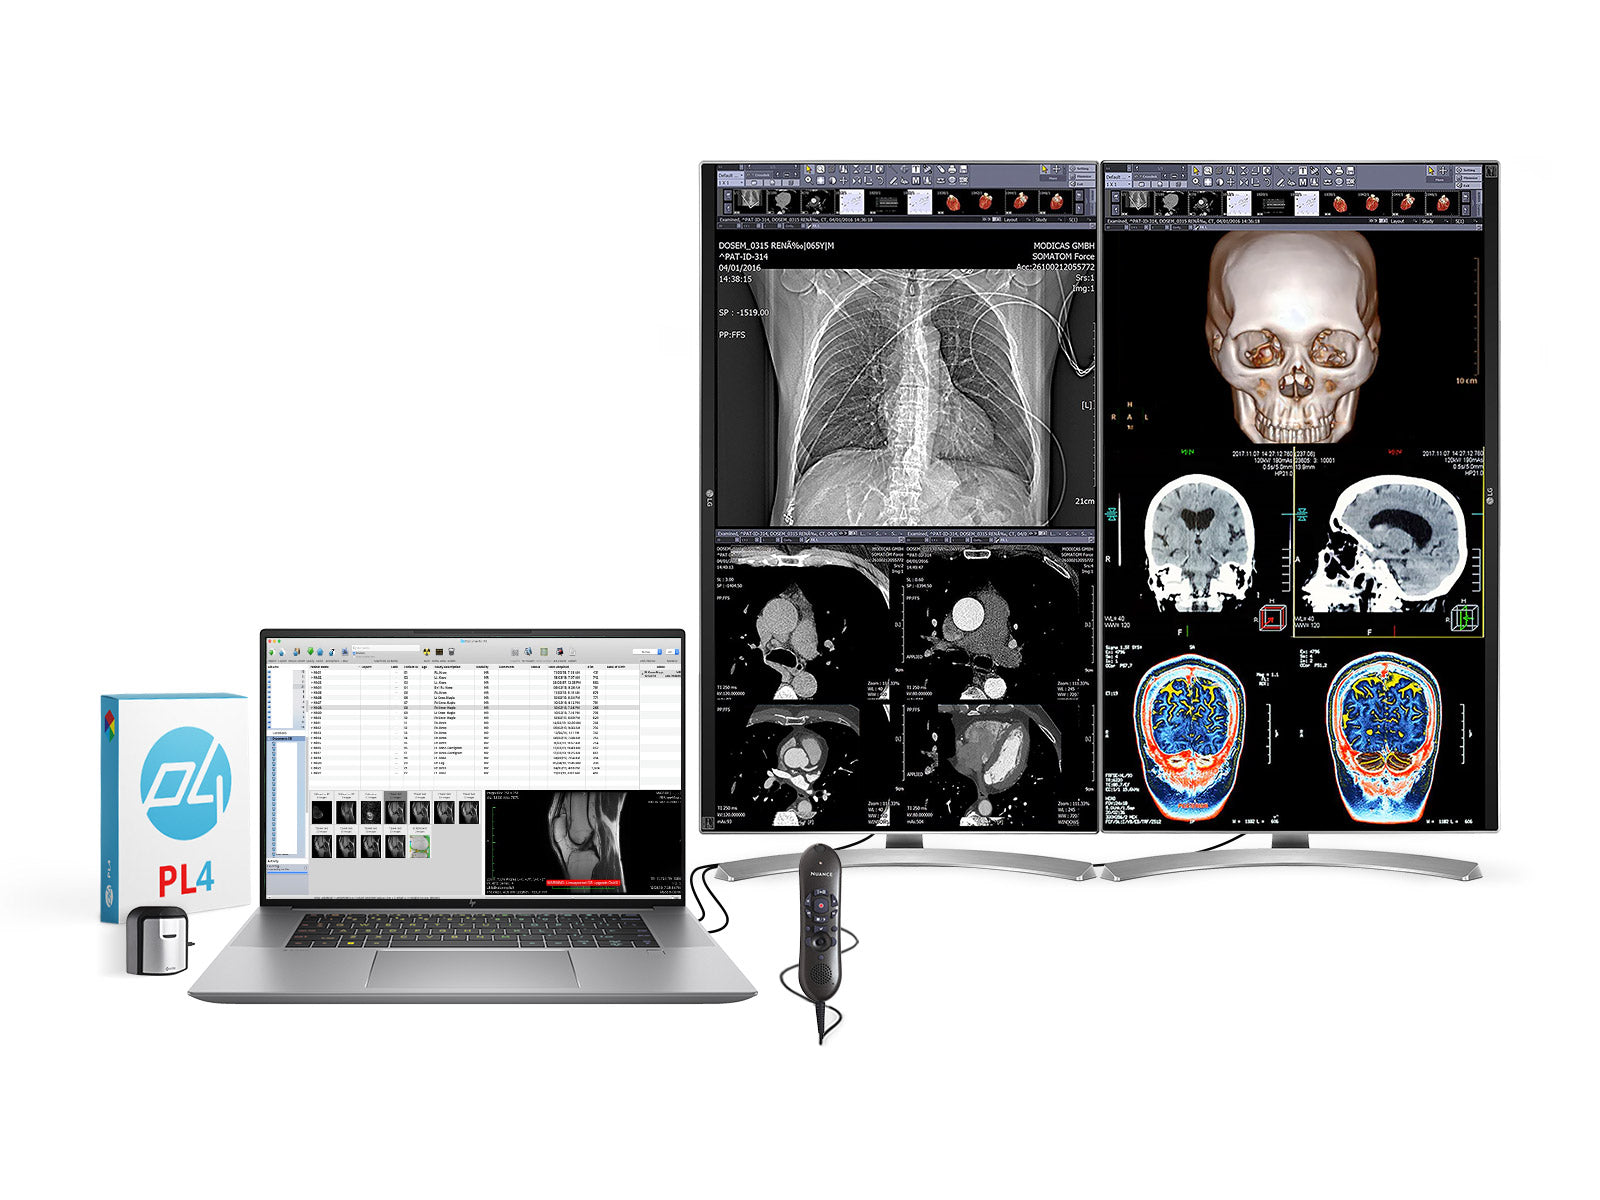

Complete PACS General Radiology Station | Barco 6MP MDCC-6230 Display | HP Workstation | Dictation Mic | Worklist Monitor (6230Z4R)

Complete PACS General Radiology Station | Barco 6MP MDCC-6230 Display | HP Workstation | Dictation Mic | Worklist Monitor (6230Z4R)

Complete PACS General Radiology Reading Station | Barco 6MP MDCC-6430 | HP Workstation | Dictation Mic | 24" Worklist Monitors (6430Z4R)

Complete PACS General Radiology Station | Barco Coronis MDCC-6330 6MP Color LED Display | HP Workstation | Dictation Mic | Worklist Monitor (6330Z4R)

Barco Coronis Fusion MDCC-6430 6MP 30″ Radiology PACS Display + Lenovo ThinkStation P3 Tiny i9‑14900 64GB DDR5 Workstation + Philips SpeechMike Trackball Dictation Mic + Dual 24″ HD Worklist Monitors + Barco MXRT‑4700 GPU + Lenovo Keyboard & Mouse

Complete PACS General Radiology Station | Barco Coronis MDCC-6430 6MP Color LED Display | HP Z4 G5 Workstation | Dictation Mic | Worklist Monitor (6430Z4G5)

Complete Clinical Review Reading Station | 2 x LG 27M-W 27" 8MP Color Clinical Review Displays | HP ZBook Studio 16 G9 | Dictation Mic | PerfectLUM Calibration Package (LGHP16G9)